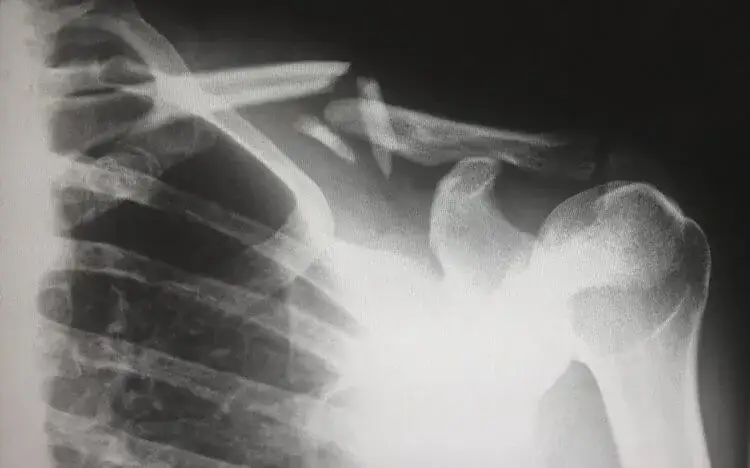

Czas rehabilitacji przy złamaniach z przemieszczeniem – różnice

Rehabilitacja po złamaniach obojczyka z przemieszczeniem zazwyczaj trwa dłużej niż w przypadku prostych złamań. W takich sytuacjach czas powrotu do zdrowia może wynosić od 6 do 12 miesięcy, w zależności od stopnia skomplikowania urazu oraz zastosowanej metody leczenia. Złamania z przemieszczeniem często wymagają interwencji chirurgicznej, co dodatkowo wydłuża czas rehabilitacji. Po operacji pacjenci muszą przejść przez intensywniejszy proces rehabilitacji, aby przywrócić pełną funkcjonalność ramienia.

W przypadku złamań z przemieszczeniem, wyzwania związane z rehabilitacją obejmują większe ryzyko powikłań, takich jak niedostateczne gojenie się kości czy ograniczenie zakresu ruchu. Dlatego tak istotne jest, aby pacjenci ściśle przestrzegali zaleceń lekarzy i fizjoterapeutów. W kolejnych sekcjach artykułu przyjrzymy się czynnikom, które wpływają na długość rehabilitacji oraz metodom leczenia, które mogą wpłynąć na powrót do zdrowia.